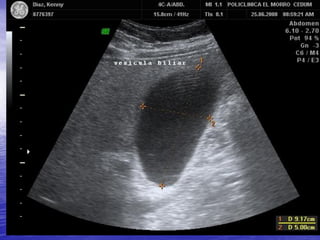

VESICULA BILIAR

ANATOMIA NORMAL DE LA

•

Visible

Fundus variable

Cuello Fijo

Forma y tamaño variable

Volumen Vesicular de 30 a 50cc

Pared Vesicular menor a 2 mm